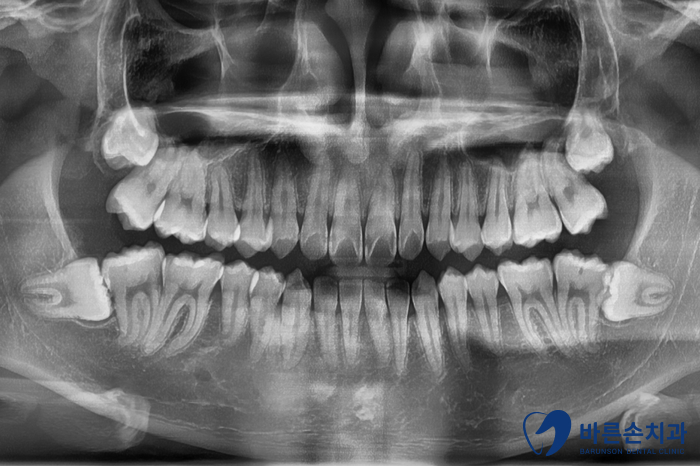

정밀한 진단을 위해 엑스레이도 촬영 해보았습니다.

충치 범위가 생각보다 넓었지만

환자 분 나이가 아직 많이 어린 학생 분이라

신경치료 없이 보철치료를 하기로 합니다.

조심스럽게 충치를 제거 한 후

큰 앞니 두개는 지르크라운 보철치료

양 쪽 작은 앞니 두개는 레진 치료로 결정!